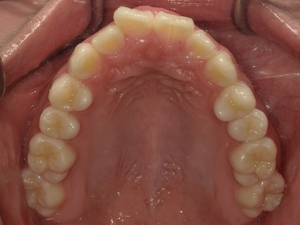

〇ご相談内容:歯のねじれが少し気になる〇矯正の種類:マウスピース型矯正「インビザライン」〇治療期間:14週間〇治療費用:44万円(税込)